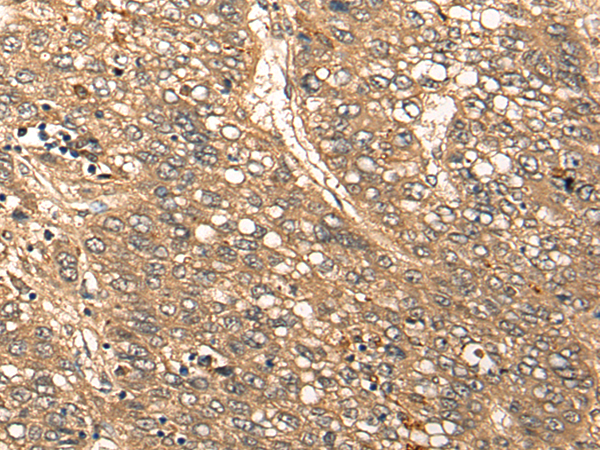

IHC positive control: |

Human liver cancer |

IHC Recommend dilution: |

25-100 |